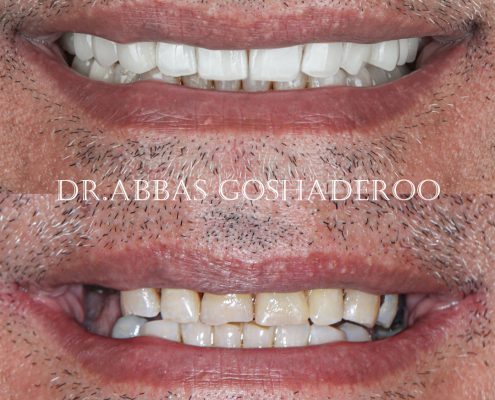

دکتر عباس گشاده رو متخصص ایمپلنت

دکتر عباس گشاده رو متخصص ایمپلنت در تهرانتلفن: 02126706197